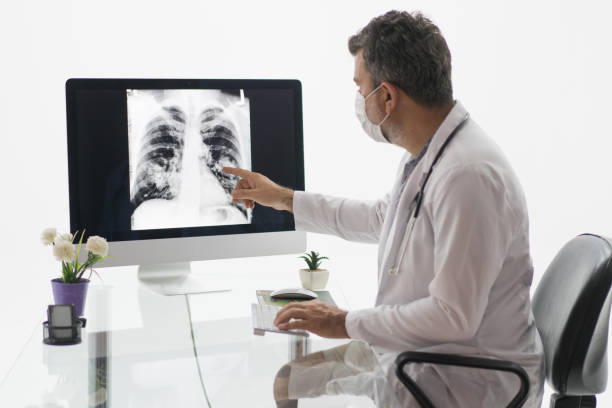

폐암 초기증상과 예방 알아보기

1990년대 암환자의 5년 생존율은 40%에 불과했지만 최근에는 약 70%까지 증가한 것으로 파악되며, 폐암과 같이 생존율이 낮았던 암들의 생존율도 크게 높아지고 있습니다. 생존율은 초기에 발견하여 대처하는 것이 좋기 때문에 이번 기회에 폐암 초기 증상을 알아보시고 인지하는 것이 중요합니다.